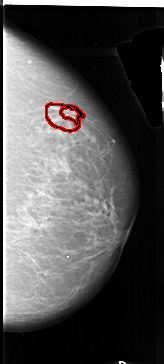

A_1012_1.LEFT_CC

RIGHT_CC LINES 6541 PIXELS_PER_LINE 2941 BITS_PER_PIXEL 16 RESOLUTION 42 OVERLAY

FILE: A_1012_1.RIGHT_CC.OVERLAY

TOTAL_ABNORMALITIES 1

ABNORMALITY 1

LESION_TYPE MASS SHAPE IRREGULAR MARGINS SPICULATED

ASSESSMENT 4

SUBTLETY 2

PATHOLOGY MALIGNANT

TOTAL_OUTLINES 2

BOUNDARY

CORE